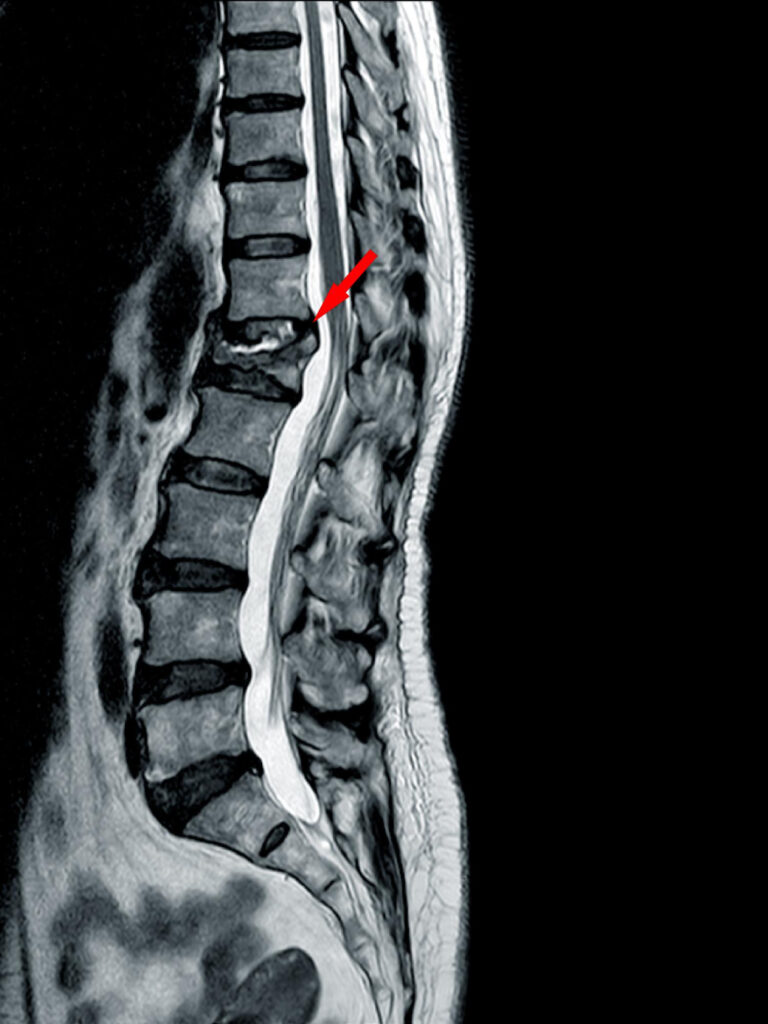

If you’re struggling with chronic back pain, herniated discs, or sciatica, spinal decompression therapy in McKinney, TX may be the non-surgical solution you’ve been looking for. At Dr. O Chiropractic, we specialize in spinal decompression — a gentle, effective treatment designed to relieve pressure on the spine, restore disc health, and promote long-term healing.

Spinal decompression is a non-invasive therapy that gently stretches the spine to reduce pressure on compressed discs and nerves. This process helps create space between vertebrae, allowing oxygen, water, and essential nutrients to flow back into the discs — fueling natural repair and recovery.

Spinal decompression therapy can benefit patients suffering from:

Herniated or bulging discs

Degenerative disc disease

Sciatica or nerve compression

Chronic low back pain

Disc-related neck pain

By restoring spinal alignment and relieving disc pressure, this therapy helps reduce pain, improve mobility, and prevent future flare-ups.